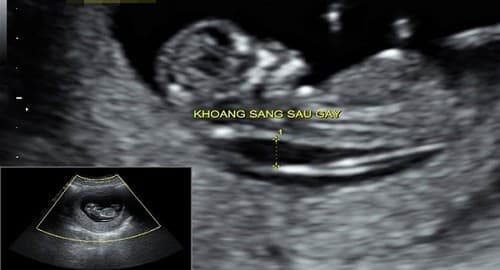

Độ dày da gáy hay còn gọi khoảng sáng sau gáy là sự kết tụ chất dịch dưới da ở vùng gáy. Tất cả thai nhi ở tuổi thai từ 11 tuần đến 13 tuần 6 ngày thì đều có chất dịch này kết tụ ở vùng gáy, tuy nhiên, với thai nhi mắc hội chứng Down số lượng chất dịch này tăng lên đáng kể làm cho độ mờ da gáy tăng lên, dày hơn. Việc đo độ mờ da gáy là cách để sớm phát hiện hội chứng Down.

Độ dày da gáy hay còn gọi khoảng sáng sau gáy là sự kết tụ chất dịch dưới da ở vùng gáy.

Bác sĩ sẽ đo chiều dài từ đỉnh đầu đến cuối xương sống thai nhi, và đo độ mờ da gáy. Khoảng mờ này là đường sáng sau gáy thai nhi trong khi vùng xung quanh màu tối sẫm hơn.